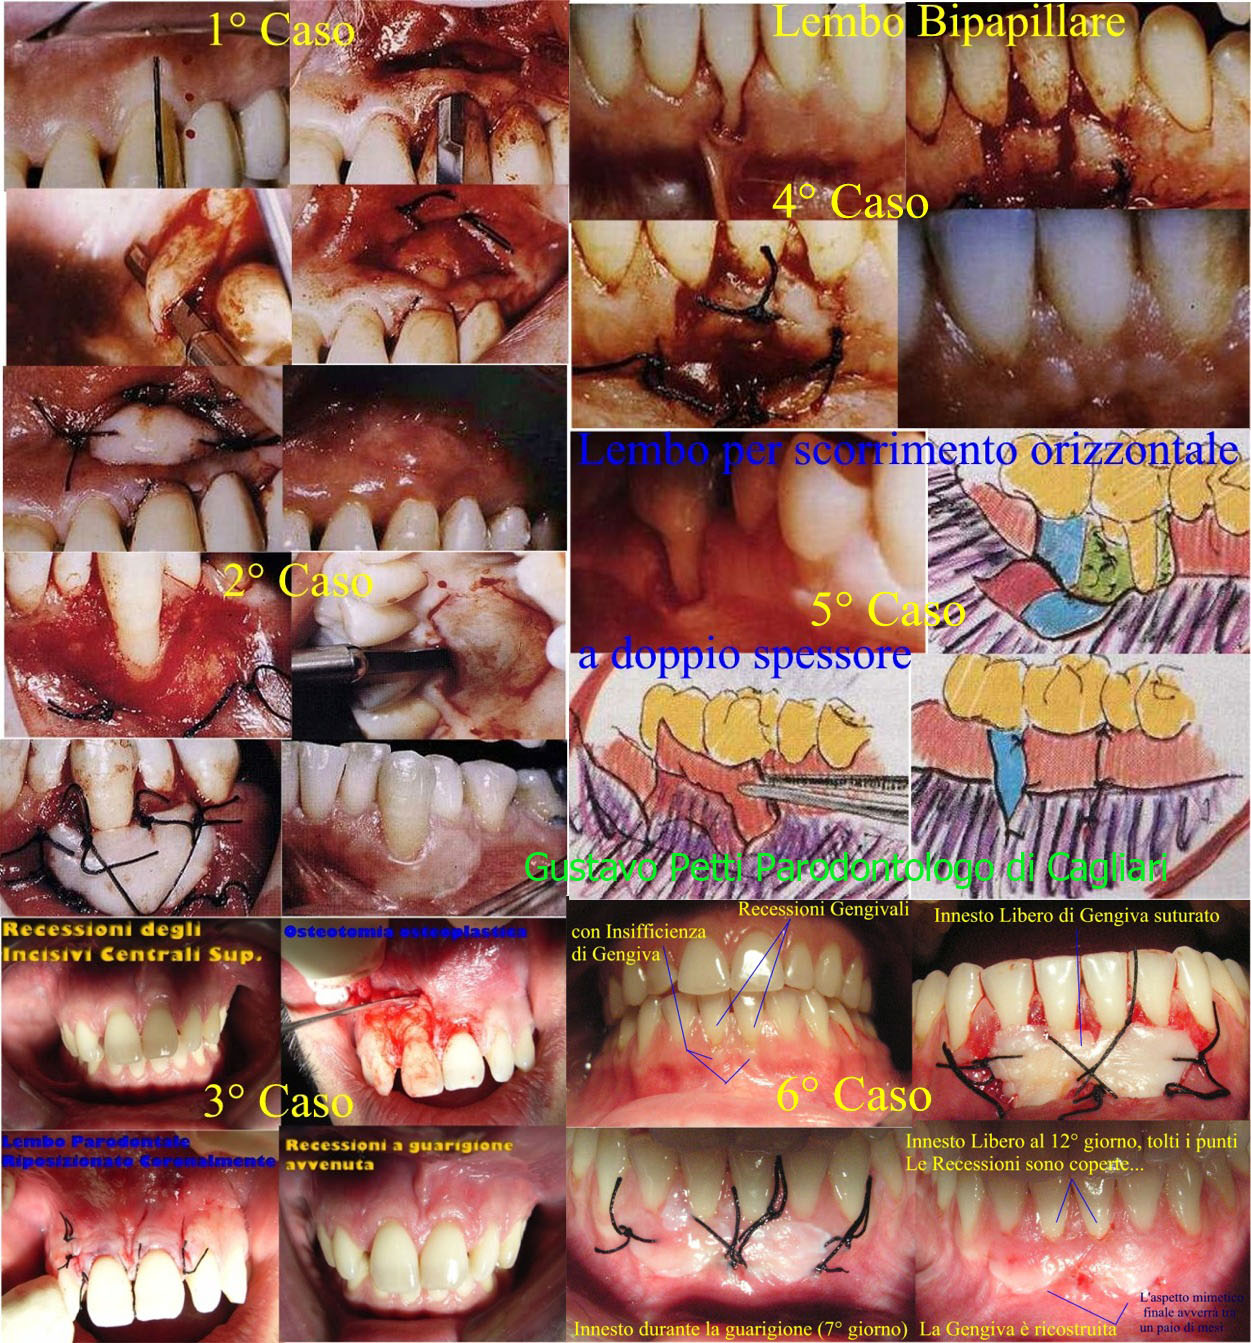

Direi che stiamo parlando di una recessione gengivale e non di una Parodontite che è tutt'altra cosa!si faccia vistare da un bravo Parodontologo. Le lascio, per capirci meglio, un poster di foto di interventi di chirurgia parodontale mucogengivale per patologie simili, se ci fossero, fatto ovviamente da me :)

Le Recessioni si possono trattare con semplcissimi interventini di chirurgia muco-gengivale parodontale estetica tipo lembi semilunare, lembi di tarnow,Innesto bilaminare e sue varianti come un lembo coronale posto a copertura di una membrana secondo i principi della GTR (Guided Tissue Regeneration = Rigenerazione tissutale guidata)! Imperativo è fare questo intervento prima di eventuali terapie di erosioni dello smalto cervicali per non alterare l'attacco epiteliale al dente! Queste sono tutte nozioni che un buon Parodontologo conosce bene! Stia tranquilla, sono "routine di tutti i giorni"! Badi che bisogna fare diagnosi differenziale tra erosione e recessione perché purtroppo non pochi odontoiatri si confondono, a volte, in situazioni in cui le una si sovrappongono e coesistono con le altre! Gli innesti liberi che vedrà tra essi sono avvenuti per la presenza di una recessione gengivale con una banda insufficiente di gengiva aderente o necessità, come l'ultimo in basso a Dx per un approfondimento del fornice,Questo per darle una idea della miriade di interventi e quindi di Diagnosi Differenziali che un parodontologo deve fare!Legga nel mio profilo "VISITA PARODONTALE" e tutto quello che vorrà leggere delle mie pubblicazioni sulla Parodontite e soprattutto sulle Recessioni Gengivali! La scelta del trattamento Ogni recessione ha il suo intervento d'elezione: i parametri più importanti da valutare, a tale proposito, sono l'integrità dell'osso alveolare e la qualità del tessuto aderente. E' ovvio che se non esiste deiscenza alveolare, la condizione è senz'altro più stabile che non se esista invece la deiscenza. Non tutte le recessioni vanno quindi curate :)Le spiego qualcosa sulle Recessioni Gengivali. Questo lo si può decidere solo clinicamente con adeguata visita parodontale. Diciamo che ogni Recessione ed ogni zona della bocca necessitano di interventi adatti e mirati! Questa è serietà! Non si vende il "fumo", si vende "l'arrosto"! :) Infatti la morfologia delle recessioni è varia: possono assumere l'aspetto di fessure verticali che attraversano la banda di gengiva aderente (fessure di Stilman), oppure di perdita parziale o totale della gengiva aderente che ricopre la radice. La classificazione più comune è quella di MILLER, che prende in considerazione l'aspetto clinico e lo stato osseo interprossimale, in particolare delle piramidi ossee sottopapillari: prima classe ; recessioni che non si estendono fino alla giunzione mucogengivale e nelle quali non vi è perdita di osso e di tessuti molli interprossimali. seconda classe ; recessioni che raggiungono o superano la giunzione mucogengivale, non vi è perdita di osso e di tessuti molli interprossimali terza classe ; recessioni che superano o raggiungono la giunzione mucogengivale con perdita di osso o tessuto molle apicalmente alla giunzione amelocementizia, ma coronale all'estremità apicale della recessione. quarta classe ; recessioni che superano la giunzione mucogengivale con perdita ossea interprossimale fino ad un livello apicale rispetto alla base della recessione.